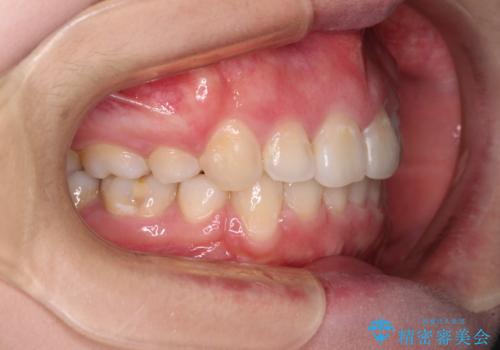

- 前歯のデコボコを気にして来院された患者様です。

当初は口元の突出感はあまり気にされていない様子だったので、インビザラインによる非抜歯矯正をお勧めしたが、ふっくらとした口元を改善したいとのことで、積極的に口元の突出感を改善することとしました。

上下左右第一小臼歯4本の抜歯を行い、ワイヤー装置による矯正治療を行うこととしました。